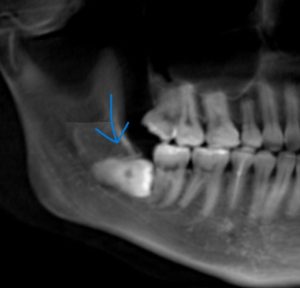

歯は骨の中に埋まっている

歯は、あごの骨に直接くっついているわけではなく、

・歯

・歯根膜(クッションのような組織)

・骨

という構造になっています。

この「歯根膜」があることで、

歯は少し動くことができます。